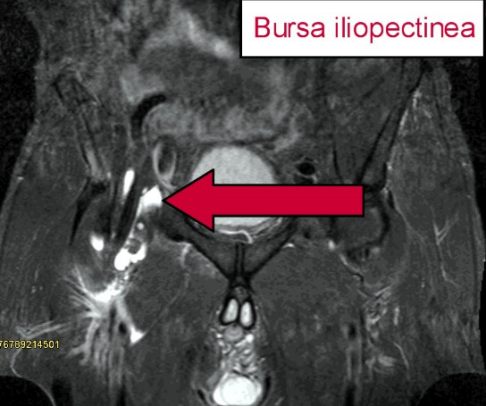

Schleimbeutelentzündung in der Leiste: Bursitis iliopectinea

Die Bursa iliopectinea ist ein großer Schleimbeutel im Bereich der Leiste. Er befindet sich an der Eminentia iliopubica, eine Knochenerhöhung zwischen Schambein (Os pubis) und Darmbein (Os ilium) im inneren Becken. Seine Aufgabe ist die Polsterung des Musculus iliopsoas (Hüftbeuger) gegenüber dem Hüftknochen. Ebenso wie die Bursitis trochanterica entsteht die Bursitis iliopectinea durch Überlastung und einseitige Bewegungen.

Da die Schleimbeutelentzündung tief in der Leiste lokalisiert ist, sind meist keine äußeren Symptome wie Rötungen oder Schwellungen sichtbar. Betroffene verspüren Schmerzen in der Leiste, die sich durch äußeren Druck verstärken.

MRT-Bild einer Bursitis iliopectinea: Der Pfeil deutet auf den entzündeten Schleimbeutel. Da er mit entzündlicher Flüssigkeit gefüllt ist, erscheint der Schleimbeutel in der Bildgebung weiß. © Gelenk-Klinik